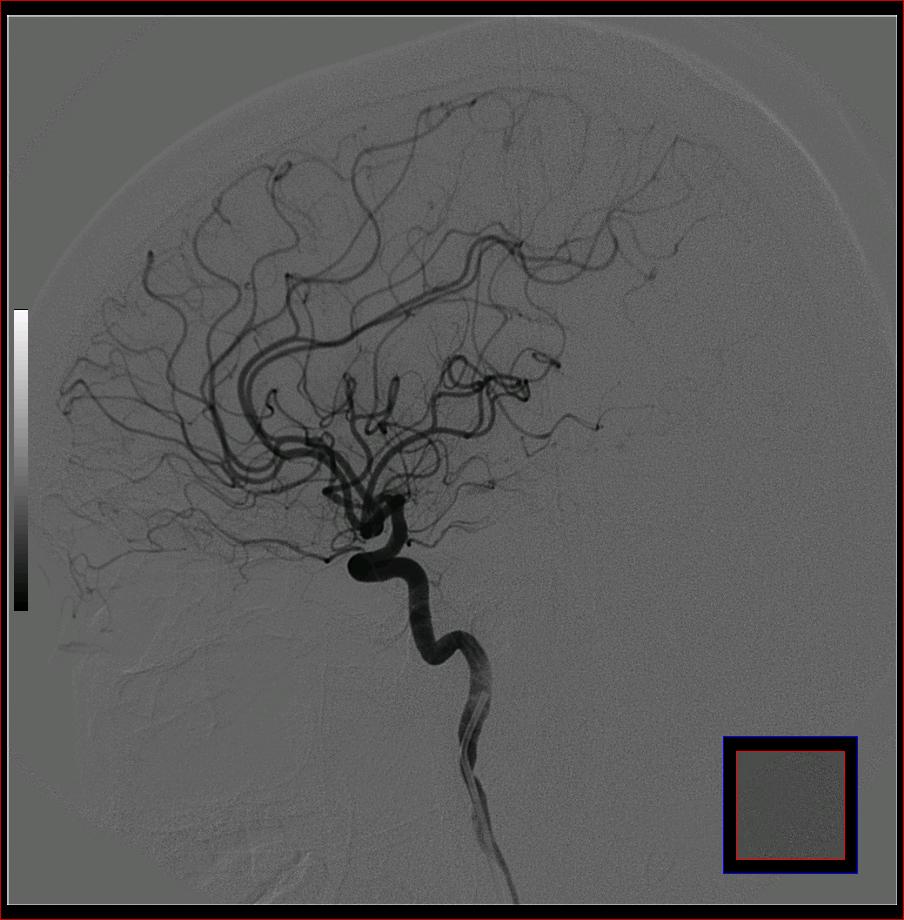

标题: DSA0121:脑血管造影

男,65岁,肢体无力。

左侧大脑中动脉水平段狭窄.

右侧大脑前a缺如.左侧大脑中动脉m1段狭窄,远端分支分布稀疏.

右侧大脑前a缺如.左侧大脑中动脉m1段狭窄

前交通或稍远端动脉瘤要仔细查,左大脑中动脉狭窄要鉴别,有可能是痉挛,因为造影导管插得稍深啦。其它就是供血动脉变异较大